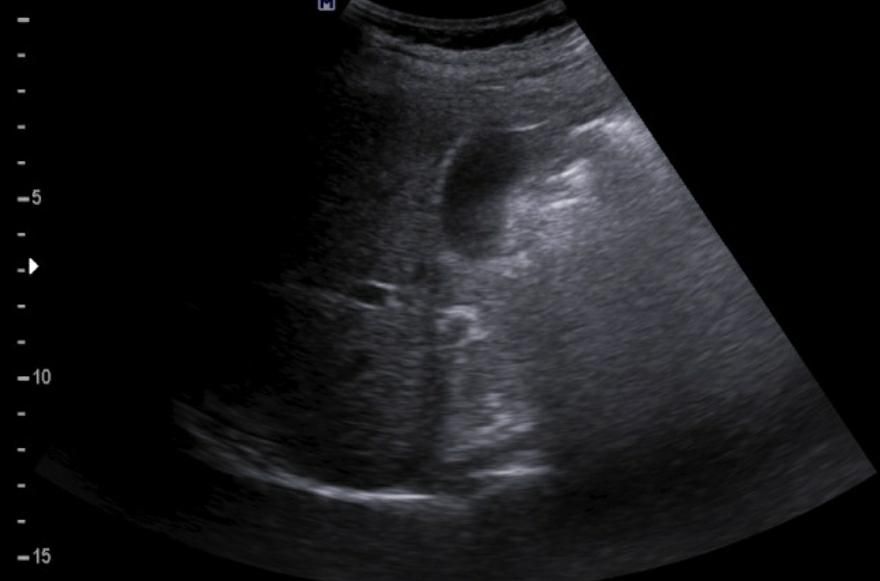

간에 혹이 있는건가요? 초음파 사진 봐주세요

간에 혹이 있는건지 맞다면 크기나 모양이 혈종인지 아이면 암으로 의심이 되는지 초음파 사진 봐주세요...ㅜㅜㅜ꼭 답변 부탁드립니다

• 2번 째 사진

간 초음파로만 봐서는 약간의 지방간이 관찰되지만 혈종으로 의심되지는

않으며 사진 우측에 보이는 동그란 부분은 장의 단면이 관찰되었을 가능성이

높은 것으로 보입니다